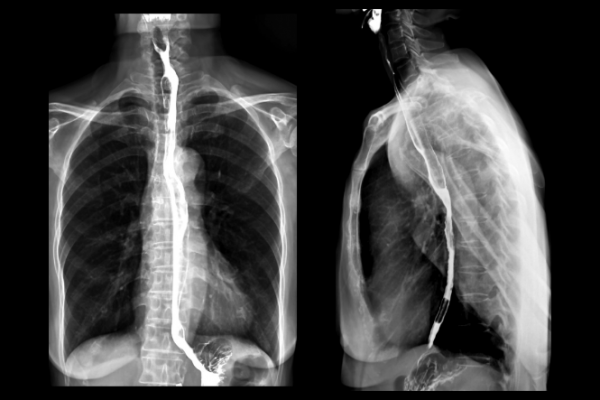

Myelogram – an imaging test to get detailed pictures of the structures of your spine and spinal cord.

Arthrogram – a procedure to look at a joint, such as your shoulder, hip or knee. Often a dye or contrast will need to be injected into the joint to show more details for a proper diagnosis. These are often done together with an MRI study

Arthrogram

Image credit: Allevia Radiology